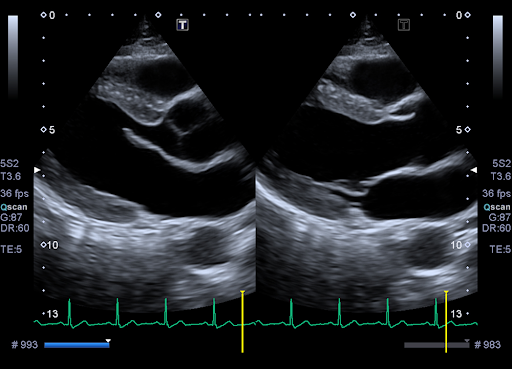

Tissue Enhancement

Эксклюзивная технология Tissue Enhancement позволяет проводить исследование у пациентов с затрудненной визуализацией за счет повышения однородности изображения и четкости очертания границ эндокарда.